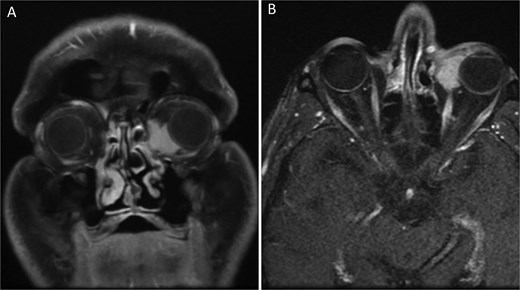

The patient’s medical history revealed that two years earlier, he had presented with a mass in the left caruncle. Subsequent investigations confirmed a diagnosis of follicular non-Hodgkin lymphoma localized solely to the caruncle. He underwent six cycles of R-Bendamustine chemotherapy. Post-treatment PET-CT scans demonstrated findings consistent with complete remission. Two years later, during a routine follow-up, the patient was found to have a recurrent mass in the same localization. The hematology department referred the patient to the ophthalmology department for further evaluation. Orbital MRI revealed a lesion measuring ~23 × 34 mm at the level of the left medial orbital wall, extending to the inferior wall (Fig. 2A–B), suggestive of orbital lymphoma, with a recommendation for biopsy. An incisional biopsy was performed on the left caruncular mass, and the mass was excised from the caruncle (Fig. 3). Histopathological analysis confirmed a diagnosis of follicular lymphoma. Following the biopsy, the patient received 16 sessions of radiotherapy.

Orbital MRI images of the patient (A) Coronal T1-weighted orbital MRI showing a well-defined lesion in the left caruncular region. The mass measures ~23 × 34 mm and extends to the medial and inferior orbital walls, with homogenous contrast enhancement. No significant infiltration into adjacent structures is observed. (B) Axial T1-weighted orbital MRI showing a homogeneously enhancing mass in the left caruncular region. The lesion extends to the medial and inferior orbital walls without significant involvement of adjacent orbital structures. The mass demonstrates clear boundaries and no evidence of periorbital tissue infiltration.